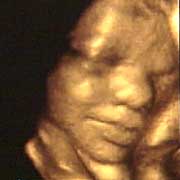

圖文:胎兒子宮內表情豐富 專家稱提供研究新依據

中新網9月13日電 英國天空新聞報道,英國科學家圖亞特·坎貝爾最近利用先進的掃描技術清晰地拍下了孕婦子宮中胎兒的表情,透過他拍攝的照片,人們可以清楚的看到一個尚未降臨世間的小生命喜、怒、哀、樂的表情。

斯圖亞特.坎貝爾是倫敦著名的產科教授,他利用超聲掃描技術拍攝到了胎兒在子宮中打呵欠、眨眼、吮手指、哭泣甚至微笑的畫面,這些都為胎兒行為的研究提供了新的依據,專家認為,這一突破將推動嬰兒健康科學的發展,包括對唐氏綜合癥等嬰幼兒疾病的診治將起到極大的推動作用。